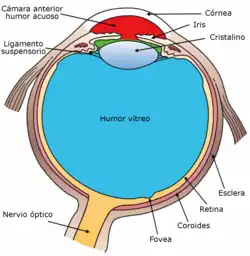

Cuando la luz penetra en el ojo, esta pasa a través de la córnea, la pupila y el cristalino, para llegar a la retina, donde la energía electromagnética de la luz se convierte en impulsos nerviosos que por medio del nervio óptico son enviados hacia el cerebro para su procesamiento por la corteza visual. En el cerebro tiene lugar el complicado proceso de la percepción visual gracias al cual somos capaces de percibir la forma de los objetos, identificar distancias, detectar los colores y el movimiento. La retina es una de las regiones más importantes del ojo y contiene unas células especializadas llamadas conos y bastones que son sensibles a la luz.[1]

El ojo es el órgano encargado de la recepción de los estímulos visuales. Cuenta con una estructura altamente especializada producto de millones de años de evolución. El ojo humano posee tres envolturas que, de fuera hacia dentro, son:

- Túnica fibrosa externa. Se compone de dos regiones: la esclerótica y la córnea.

- Esclerótica: Es blanca y opaca, con fibras colágenas tipo I entremezcladas con fibras elásticas; avascular, que brinda protección y estabilidad a las estructuras internas. Cubre la mayor parte del globo ocular, excepto en una pequeña región anterior.

- Córnea: Es una prolongación anterior transparente, avascular pero muy inervada de la esclerótica, que abulta hacia delante del ojo. Es ligeramente más gruesa que la esclerótica.

- Túnica vascular media (úvea). Está conformada por tres regiones: la coroides, el cuerpo ciliar y el iris.

- Coroides: Es la porción posterior pigmentada de la túnica vascular media, la cual se une a la esclerótica laxamente y se separa del cristalino mediante la membrana de Bruch.

- Cuerpo ciliar: Es una prolongación cuneiforme que se proyecta hacia el cristalino y se ubica en la luz del ojo entre el iris (anterior) y el humor vítreo (posterior).

- Iris: Es la extensión anterior pigmentada de la coroides, cuya función es regular la entrada de luz al ojo mediante la contracción o distensión de la pupila.

- Retina o túnica neural. Es la porción del ojo sensible a la luz, en la que se encuentran las células especializadas llamadas conos y bastones. Se compone de diez capas que, desde el exterior al interior, se denominan epitelio pigmentado, capa de conos y bastones (receptora), membrana limitante externa, capa nuclear externa, capa plexiforme externa, capa nuclear interna, capa plexiforme interna, capa de células ganglionares, capa de fibras del nervio óptico y membrana limitante interna.

Los rayos paralelos de luz llegan al ojo ópticamente normal (emétrope) y se enfocan sobre la retina. Dependiendo de la especie animal, el enfoque puede resolverse aumentando la distancia entre el cristalino y la retina o aumentando la curvatura o el poder refringente del cristalino, como ocurre en los mamíferos.[5]

Al mecanismo por el cual aumenta la curvatura del cristalino se llama acomodación. Cuando la mirada se dirige a un objeto cercano, el músculo ciliar se contrae y se relaja el ligamento suspensorio del cristalino, permitiendo que este tome una forma más convexa, lo cual aumenta su poder de convergencia.

La retina posee diez capas. La luz debe atravesar casi todas estas capas para llegar hasta donde se ubican los conos y los bastones, que son las células especializadas en la recepción de los estímulos visuales y de la transformación de estas señales en impulsos nerviosos que a través del nervio óptico llegaran al cerebro para ser procesados y construir imágenes, formas, colores y movimientos.

La retina posee una compleja red de neuronas. Los conos y los bastones próximos a la coroides establecen sinapsis con las células bipolares y estas con las ganglionares, cuyos axones convergen y salen del ojo para conformar el nervio óptico. El nervio óptico sale del globo ocular en la zona posterior del ojo junto con los vasos retinianos en un punto conocido como papila óptica, en donde no existen receptores visuales, por lo que constituye un punto ciego.

Por el contrario, también existe un punto con mayor agudeza visual localizado cerca del polo posterior del ojo, denominada mácula lútea, de aspecto amarillento, y en la cual se encuentra la fóvea central, que es una pequeña porción de la retina carente de bastones pero con mayor densidad de conos. Al fijar la atención visual en un objeto determinado, la luz del objeto se hace incidir sobre la fóvea, que es lugar de la retina con máxima sensibilidad.

Tras atravesar la córnea, la luz pasa por un orificio que se encuentra en el centro del iris llamado pupila. Posteriormente atraviesa el cristalino, que es la lente ajustable del ojo humano, para enfocarse sobre la retina, que está cubierta por receptores visuales.